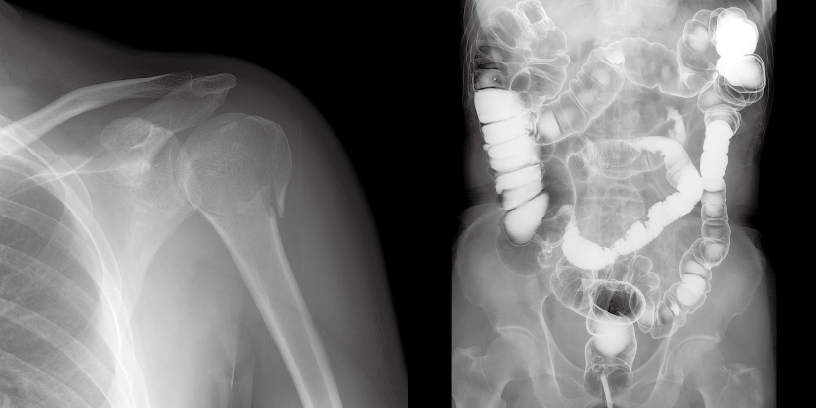

透視画像内のデバイス(ガイドワイヤーやチューブ)の視認性を向上します。WOWはデバイスを強調し、その他の背景部を減算処理します。特に椎体と重なるデバイスの視認性が向上します。私たちが提案する「透視のカタチ」です。

周波数帯域ごとに輪郭強調効果およびハレーションや黒つぶれの抑制を実行し、視認性を向上します。マルチ周波数処理は、透視画像や撮影画像内の構造に応じて、適切な強調度合いにします。Retinex理論は画像全体のコントラストを維持したまま局所ごとのコントラストを補正します。

HIREZOOMは、FPD上の1画素をディスプレイ上の1データとしてダイレクトに表示。撮影像と同等の解像度を実現する透視像が表示します。治療におけるステントやガイドワイヤーなどの視認性が向上します。IntelliFRAMEとの併用でさらに視認性を向上します。